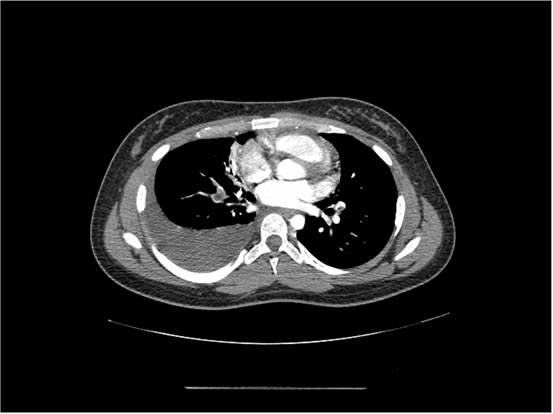

We ordered a CT scan with infusion of the chest

I will show you 12 CT-scan cuts.